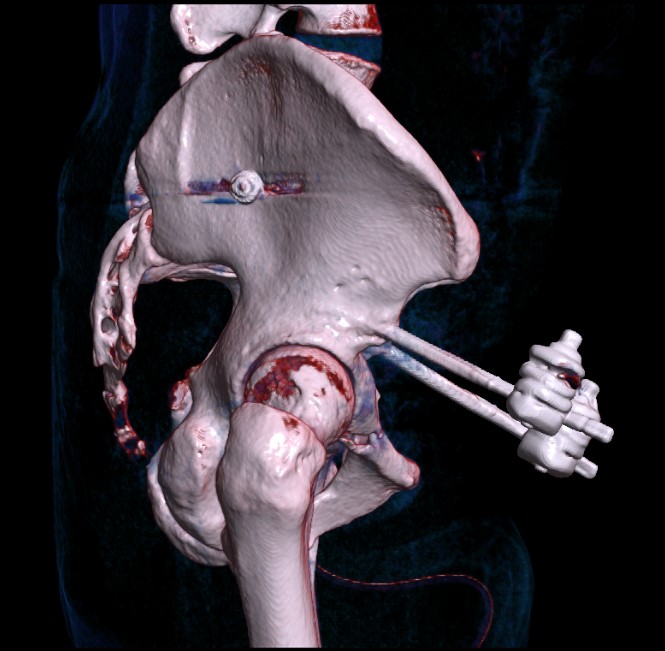

Posterior fixation

Percutaneous sacroiliac screws

Posterior approach + / - plates

Percutaneous ramus screw

Vumedi pubic rami screw and IM nail

AO surgery reference pubic rami screw